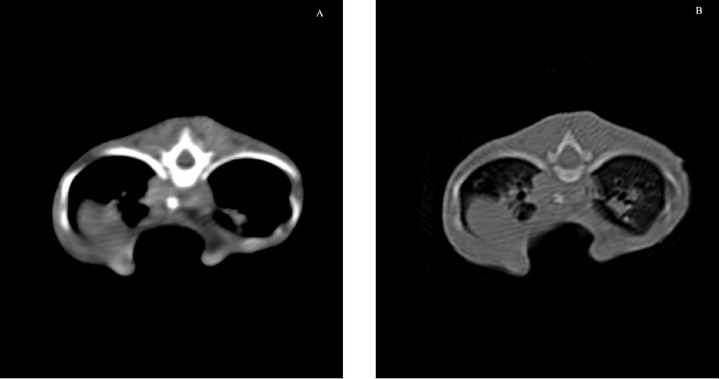

Fig. 1. Left lateral radiographic view of the thorax of the cat with pectus excavatum. Comparison of patient’s thorax before (A) and after (B) surgical treatment at 9 months postoperatively.

Fig. 2. Ventrodorsal radiographic view of the thorax of the cat with pectus excavatum. Comparison of patient’s thorax before (A) and after (B) surgical treatment at 9 months postoperatively.

Radiographic examination revealed severe dorsal displacement from the fifth sternebra to the xiphoid cartilage and a dorsal displacement of the cardiac silhouette on the lateral view (Fig. 1A), and a left mediastinal shift and compression of the left pulmonary lobes on the ventrodorsal view (Fig. 2A). VI and FSI were measured on the radiographs, being 3.2 and 9.1, respectively. The authors decided to measure these two indices also at the level of T9 because this vertebra corresponded to the point of minimum height of the thorax. VI and FSI at the level of T9 were 2.3 and 15.2, respectively. The authors measured also the minimum thoracic height (MinTH) that resulted 4.3 mm, at the level of the last sternebra.

Radiographs were obtained as previously described at each follow-up examination (Figs. 1B and 2B). IV, FSI, and MinTH were calculated and the values are reported in Table 1.

Four months postoperatively the kitten increased her body weight from 550 to 2,436 g and the skeletal deformity was dramatically improved at physical examination. No episodes of dyspnea or exercise intolerance were noticed by the owner. The VI and FSI measured on the radiographs obtained 4 months after surgery were 10.2 and 2.0, respectively. The same indexes measured at the level of T9 were 8.8 and 2.3, respectively, and MinTH was 21 mm.

Nine months postoperatively the cat underwent an ovariohysterectomy with no anesthetic-related complications. The cat was discharged from hospital 6 hours postoperatively and recovered uneventfully. Radiographs were obtained as previously described before the surgery. VI and FSI resulted in 12.4 and 1.5, respectively; the same indexes measured at the level of T9 were 9.4 and 2.1, respectively, and MinTH was 26 mm.